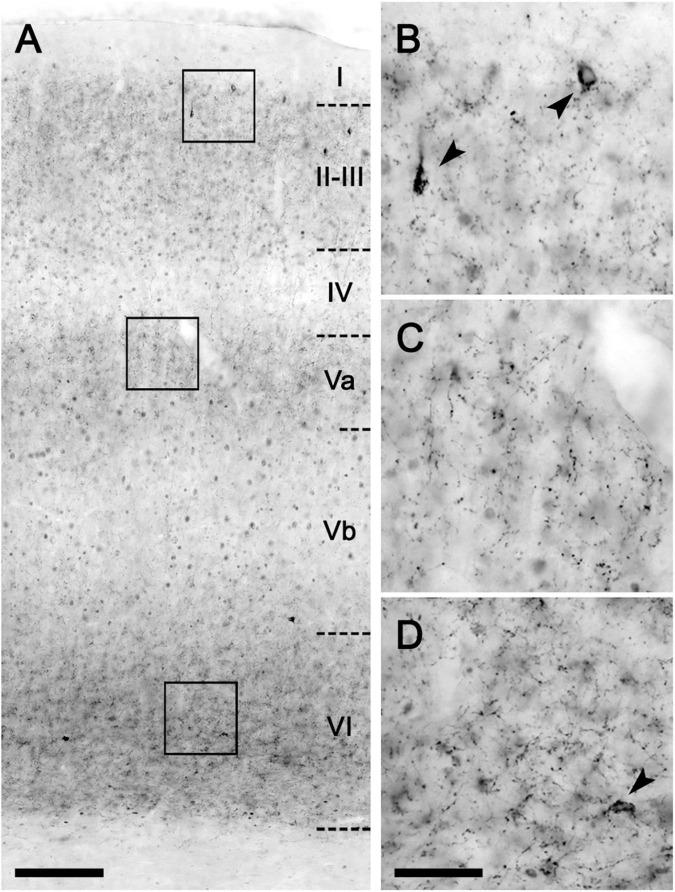

The present study describes a detailed neuroanatomical distribution map of the cannabinoid type 1 (CB) receptor, along with the biochemical characterization of the expression and functional coupling to their cognate G proteins in the medial prefrontal cortex (mPCx) of the obese Zucker rats. The CB receptor density was higher in the prelimbic (PL) and infralimbic (IL) subregions of the mPCx of obese Zucker rats relative to their lean littermates which was associated with a higher percentage of CB receptor immunopositive excitatory presynaptic terminals in PL and IL. Also, a higher expression of CB receptors and WIN55,212-2-stimulated [S]GTPγS binding was observed in the mPCx but not in the neocortex (NCx) and hippocampus of obese rats. Low-frequency stimulation in layers II/III of the mPCx induced CB receptor-dependent long-term synaptic plasticity in IL of area obese Zucker but not lean rats. Overall, the elevated 2-AG levels, up-regulation of CB receptors, and increased agonist-stimulated [S]GTPγS binding strongly suggest that hyperactivity of the endocannabinoid signaling takes place at the glutamatergic terminals of the mPCx in the obese Zucker rat. These findings could endorse the importance of the CB receptors located in the mPCx in the development of obesity in Zucker rats.

本研究描述了1型大麻素(CB)受体详细的神经解剖分布图谱,以及肥胖Zucker大鼠内侧前额叶皮质(mPCx)中该受体的表达生化特征及其与同源G蛋白的功能偶联。相对于瘦的同窝仔鼠,肥胖Zucker大鼠mPCx的前边缘(PL)和下边缘(IL)亚区域中的CB受体密度更高,这与PL和IL中CB受体免疫阳性兴奋性突触前终末的比例更高有关。此外,在肥胖大鼠的mPCx中观察到CB受体和WIN55,212-2刺激的[S]GTPγS结合的表达更高,但在新皮质(NCx)和海马中未观察到。对肥胖Zucker大鼠而非瘦大鼠的mPCx的II/III层进行低频刺激,可在IL中诱导CB受体依赖性的长期突触可塑性。总体而言,2-花生四烯酸甘油(2-AG)水平升高、CB受体上调以及激动剂刺激的[S]GTPγS结合增加,强烈表明内源性大麻素信号传导的亢进发生在肥胖Zucker大鼠mPCx的谷氨酸能终末。这些发现可能支持位于mPCx的CB受体在Zucker大鼠肥胖发生中的重要性。